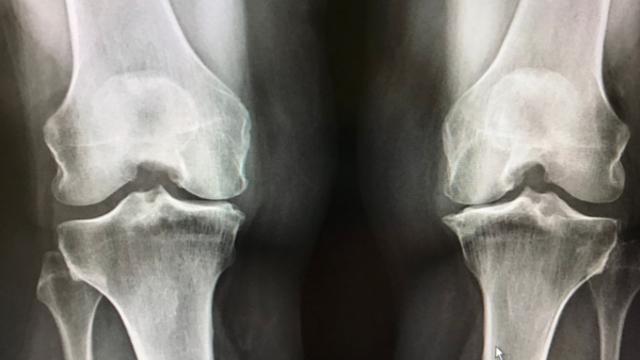

무릎은 왜 이렇게 쉽게 아플까?

데일리 포스트 2024.09.24